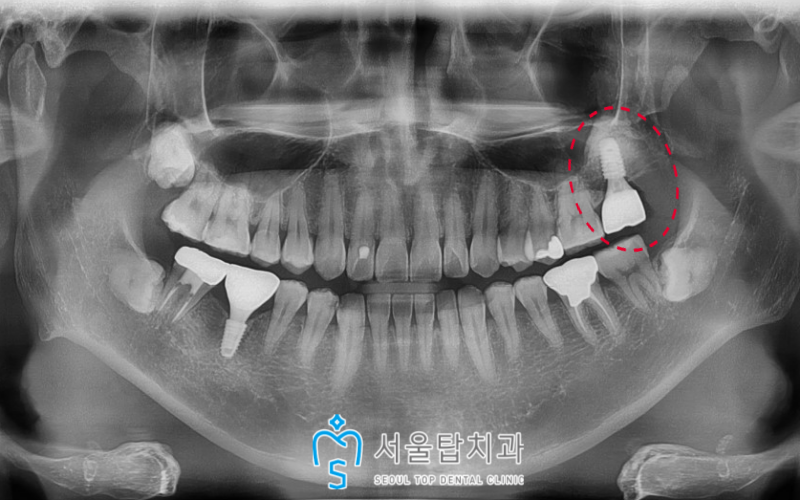

시간이 지나고,

발치 후 3개월 뒤

임플란트 식립을 진행하였고,

왼쪽 위 두 번째 어금니(#27) 부분에

상악동이 많이 내려와 있어

이 경우 바로 식립이 어렵기 때문에

상악동 거상술 및 뼈이식을 병행한

임플란트 식립을 해주었답니다.